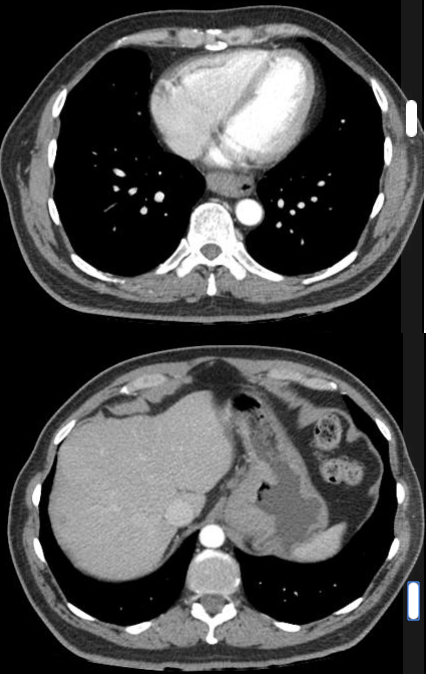

RN a termo.

Cardiomegalia massiva em um neonato com pulmão normal (sem edema alveolar ou intersticial, sem derrame pleural)

Cardiomiopatia neonatal.